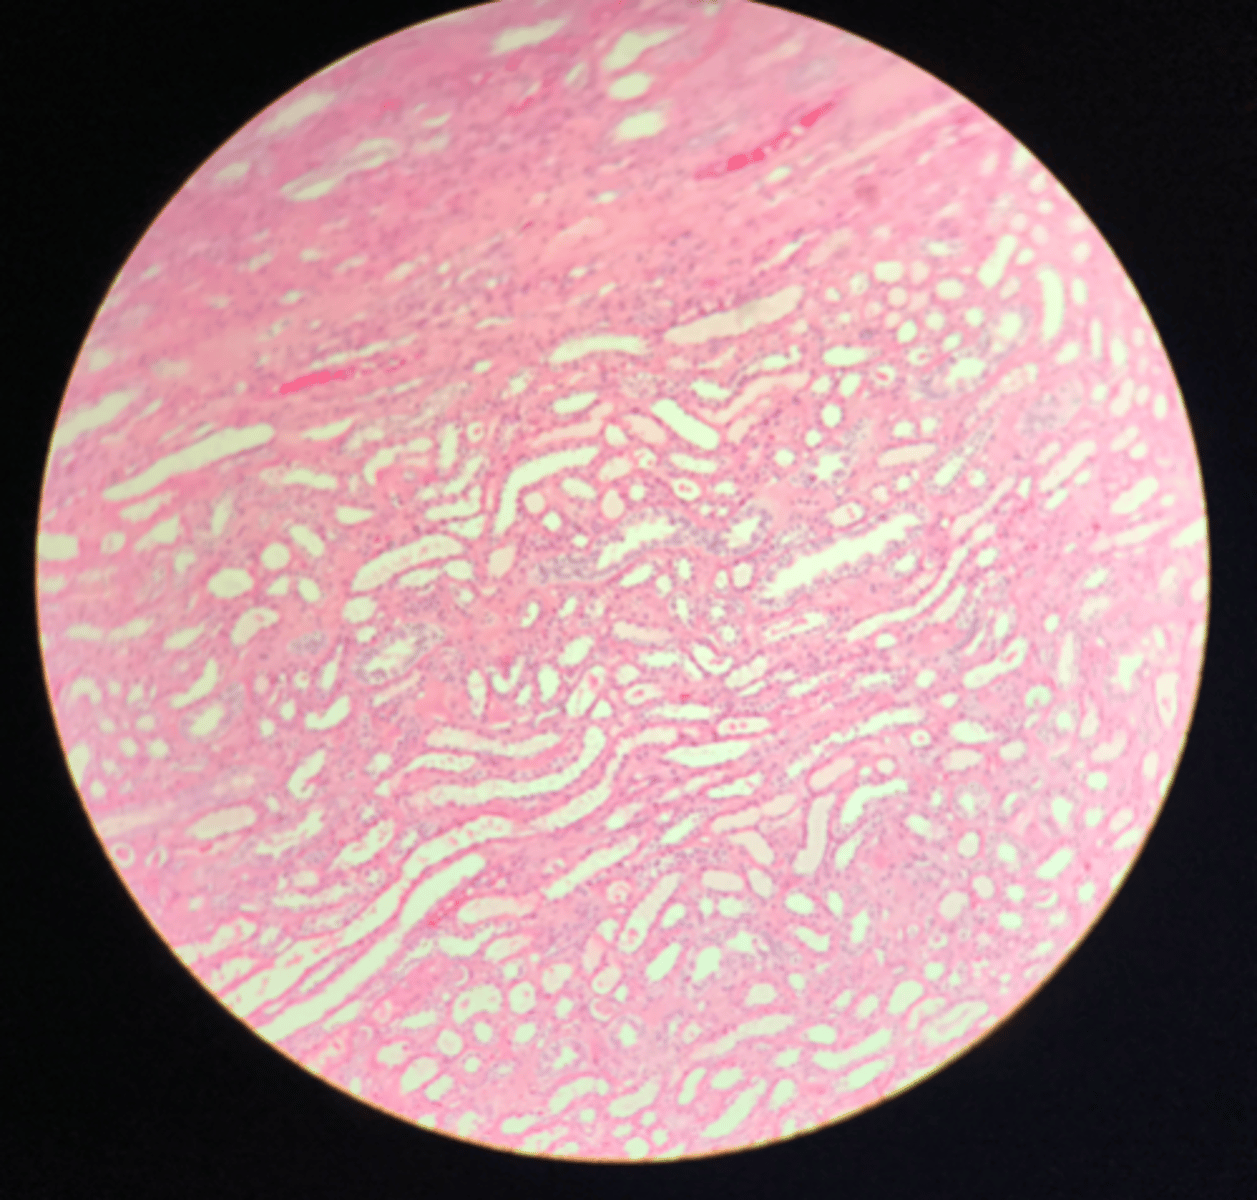

Medulla of the kidney

There are no glomerular corpuscles present and there are numerous visible collecting ducts

What layer of tissue of which organ is depicted on this slide? How can you tell?

Collecting ducts (in the medulla)

What structure of the kidney are the blue arrows pointing at?